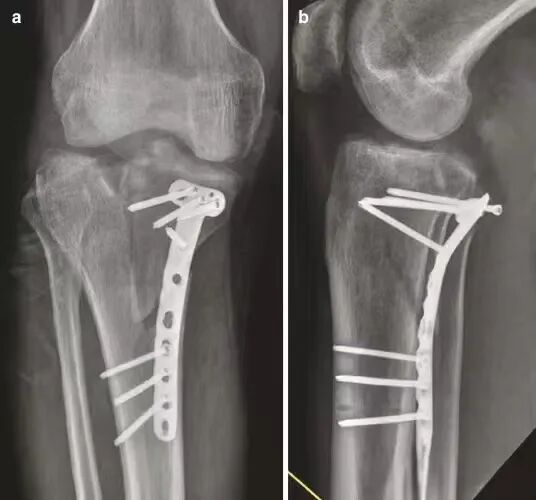

胫骨平台骨折的复位目标包括恢复胫骨平台解剖形态、重建下肢正常力线和维持关节稳定性。

胫骨平台骨折术后力线异常会改变胫骨平台 的载荷分布和应力传导,可能对膝关节短期功能影响不大,但长期容易继发PTOA,甚至需要行膝关节置换术治疗。

术后膝关节冠状面或矢状面力线异常(≥5°)是导致患者行膝关节置换的独立危险因素。

随着手术技术的进步和患者期望值的提高,胫骨平台骨折复位的标准越来越严格,不仅要关注关节面复位质量,还要注重恢复膝关节稳定性和下肢 正常力线。